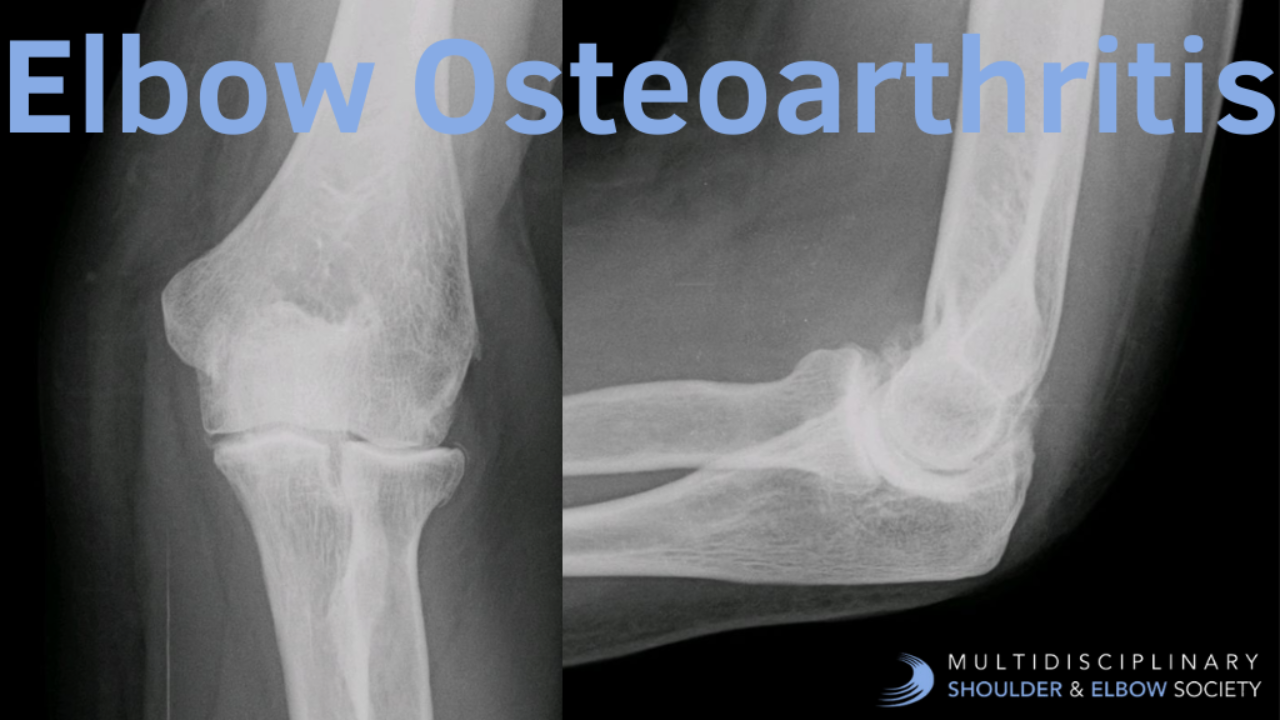

A Guide to Imaging for Elbow Osteoarthritis elbow arthritis elbow imaging elbow osteoarthritis elbow radiographs elbow x-rays osteoarthritis

A Systematic Guide to Reading Elbow Osteoarthritis Radiographs

Essential Views

Start with standard anteroposterior (AP) and lateral views of the elbow joint. For complex cases, oblique views can pro...